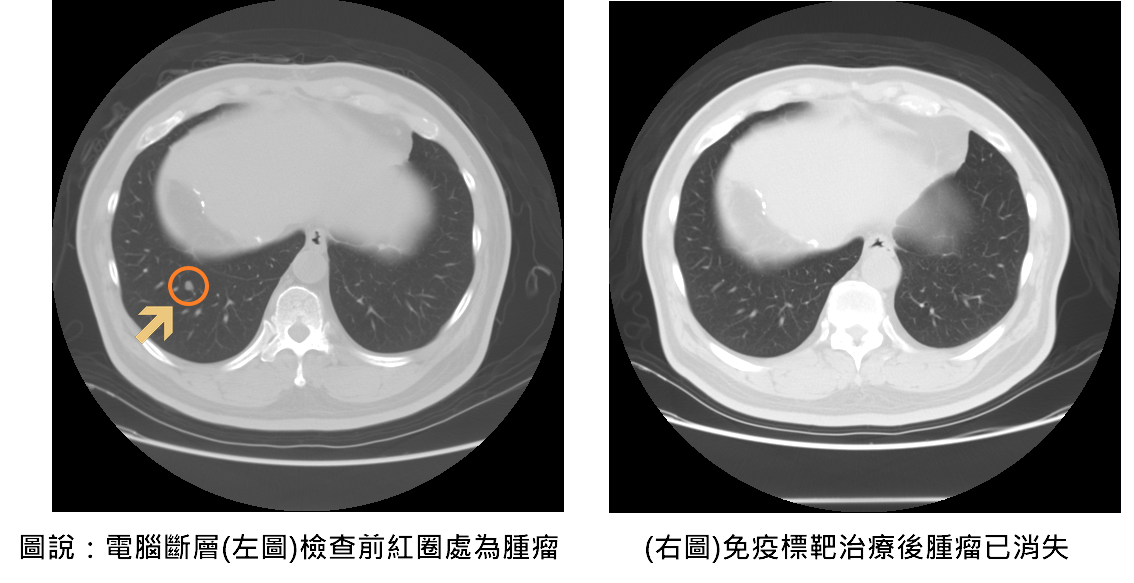

隨著2023年免疫標靶治療納入健保給付,大幅降低患者經濟負擔,也讓更多中晚期癌友得以接受有效治療。聯新國際醫院腸胃肝膽科醫師余青殷分享一位六十五歲患者,於兩年前接受肝癌切除手術,在術後例行追蹤時,發現甲型胎兒蛋白指數(AFP)持續飆高,以及肺部出現轉移的現象,經評估自體免疫狀況後,醫療團隊決定使用免疫標靶治療,採用第一線免疫標靶聯合療法—免疫藥物「癌自禦」與標靶藥物「癌思停」合併治療,三個月後AFP指數恢復正常,癌細胞亦完全消失,患者未出現任何不適或併發症,生活品質如常。

余青殷指出,過去中晚期肝癌的治療主要依賴單一標靶口服藥物,療效有限;而隨著免疫標靶聯合治療的發展,病患的整體存活期已顯著延長至近20個月,死亡風險亦降低約三成。值得注意的是,約10%以下的患者有機會成功治癒,讓腫瘤完全消失,這是以往中晚期肝癌不容易達到的效果。